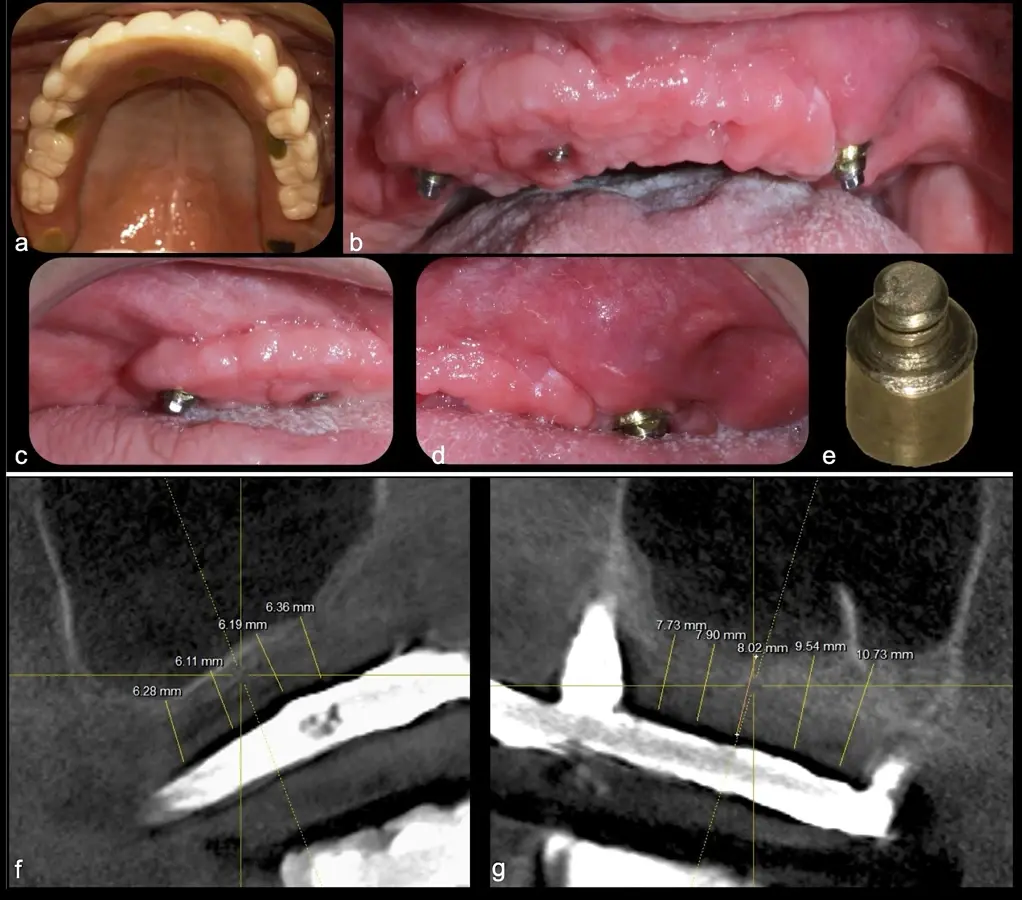

Paciente de 62 años, de sexo masculino, llega a la consulta para la colocación de implantes dentales. Refiere haber tenido tratamiento previo con implantes dentales, algunos de los cuales fueron perdidos. A la evaluación clínica se observa ausencia de piezas dentarias en el maxilar superior y 3 implantes remanentes. En la evaluación tomográfica se observa neumatización de los senos maxilares del lado derecho e izquierdo (Figura 14), para lo cual se indica el procedimiento quirúrgico de levantamiento de piso de seno maxilar en ambos cuadrantes, como paso previo a una nueva planificación implantosoportada.

Figura 14. Evaluación intraoral en donde se evidencia presencia de una prótesis híbrida soportada sobre implantes dentales, al retiro de la estructura se observó tornillo protésico fracturado (a, b, c). Evaluación tomográfica: corte sagital a nivel de los senos maxilares derecho e izquierdo, donde se observa una atrofia severa de los rebordes óseos acompañados de neumatización de los senos maxilar (d, f, g).